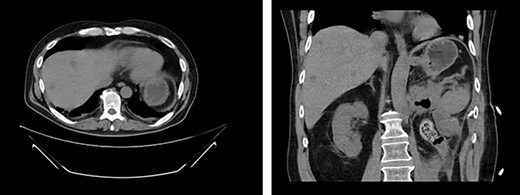

Serial CT scans at 10 and 12 weeks post-resection revealed reduction of the retroperitoneal abscess and appearance of liver lesions concerning for metastasis (Fig. 4). The patient eventually completed his radiation course with no additional problems.

First appearance of multiple liver lesions suspicious for metastasis in transverse (left) and coronal (right) planes on CT; reduction of retroperitoneal effusion can also be seen.

Fourteen weeks post-resection, the patient presented to the ED for symptoms of pneumonia and again tested positive for COVID-19. Chest X-ray showed evidence of small, right-sided pleural effusion. He was discharged for home quarantine. Ten days later, he returned to the ED with worsening shortness of breath and chest pain. CT showed a nonmalignant effusion filling the entire right hemithorax as well as significant enlargement of liver lesions (Fig. 5). He was discharged a week later following symptomatic improvement but experienced an exacerbation of respiratory symptoms soon after and was readmitted.

CT demonstrates growth of effusion into the entirety of the right hemithorax with mass effect shifting all thoracic contents to the left (left); later cytology ruled out malignant effusion; substantial increase in liver metastatic lesions can also be seen when compared to previous images from 2 months prior.